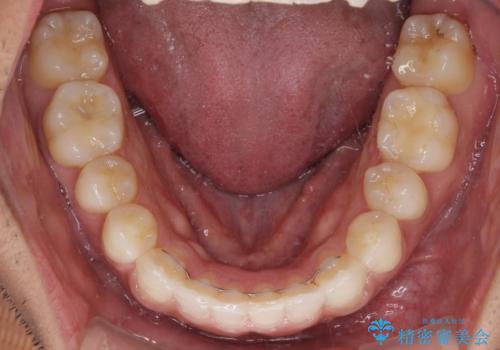

- 前歯のデコボコを治したいとのことで来院された患者様です。

上下顎ともに歯列全体の後方移動とIPR(歯と歯の間を削る)によってデコボコが解消するように設計し、インビザラインにより治療を行うこととしました。

毎日22時間以上しっかりとマウスピースを装着していただいたので、スムーズに治療が進みました。歯と歯の間を削ることでうまくスペースコントロールでき、1年強で終えることができました。